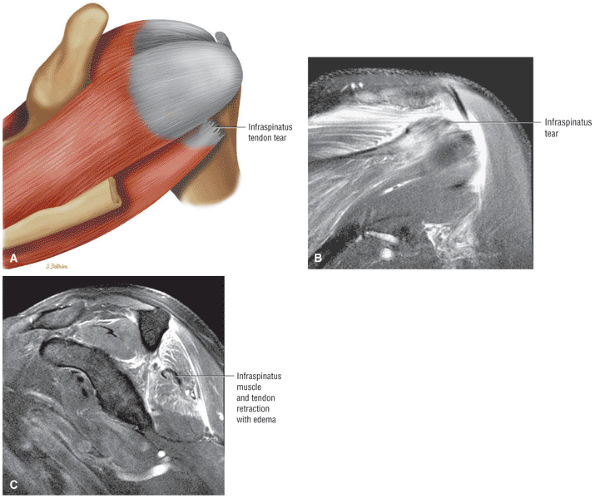

FIGURE 8.102 ● (A) The anterior undersurface of the acromion and the coracoacromial ligament form the coracoacromial arch. The subacromial subdeltoid bursa facilitates the passage of the rotator cuff and proximal humerus under the coracoacromial arch. (B) A superior axial image shows the anterior-to-posterior extent of the coracoacromial (CA) ligament perpendicular to the supraspinatus tendon. The fluid in the subacromial-subdeltoid bursa represents fluid between two serosal surfaces in contact with each other. One serosal surface is contributed by the undersurface of the coracoacromial arch and deltoid, and the other serosal surface is on the bursal side of the cuff.

|

![]() |